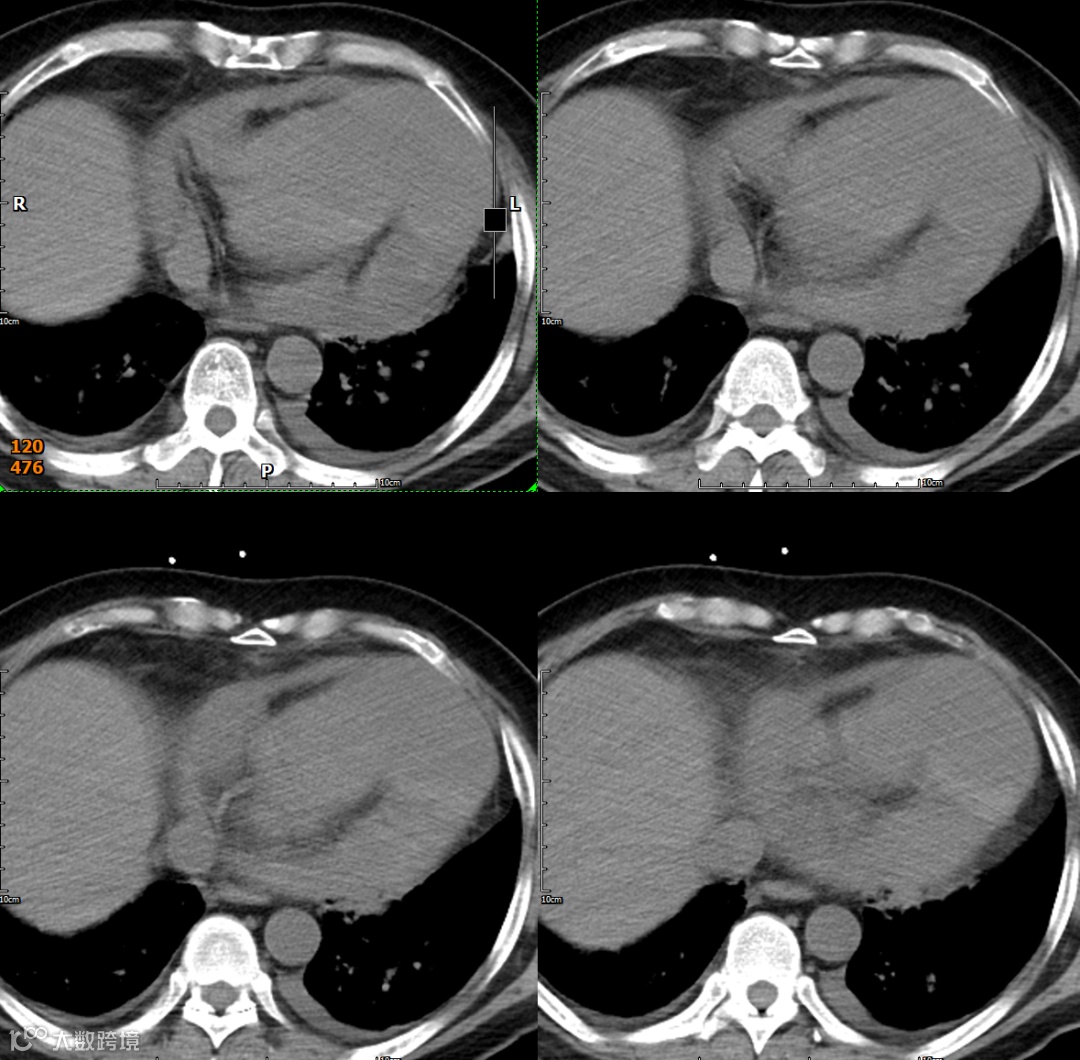

影像学检查

手术记录:纵劈胸骨正中开胸,悬吊心包,见左室明显增大,心尖部假性室壁瘤形成,大小约10cm×6cm,并与左侧心包粘连,分离室壁瘤粘连,切开假性室壁瘤见左室壁破口约8cm,切除室壁瘤体坏死变薄心肌组织

假性室壁瘤 (LVPA):

形态与位置:与左心室腔相邻的囊状、球状或葫芦状对比剂充盈腔。特征性的窄瘤颈是其关键。位置常在心包反折附近(下壁、后壁、侧壁)。

瘤壁:菲薄,无心肌密度!主要由心包(可能钙化)和血栓(不强化或延迟强化)构成。

瘤颈:清晰可见的、狭窄的开口(如瓶颈状)将假性瘤腔与左心室腔相连。破口处心室壁中断是直接征象。

腔内:可见对比剂充盈,内常有血栓(充盈缺损)。

心包:局部心包增厚、粘连、积液常见。瘤体常部分嵌入心包内。